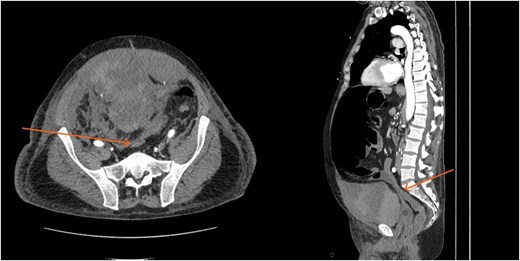

Laboratory results showed thrombocytopenia and erythrocytosis, with a hemoglobin level of 18.6 g/dl and platelets at 840 00/μl. A CT scan of the abdomen and pelvis was ordered to rule out malignancy or paraneoplastic syndrome causing the VTE (Fig. 1). The CT showed no lesions suspicious for malignancy but revealed a left RSH, managed conservatively.

A massive transfusion protocol was initiated, and the patient received four units of packed red blood cells, six units of fresh frozen plasma, two units of platelets, and bicarbonate boluses. A CT abdomen and pelvis was performed to reassess the RSH, revealing an interval enlargement (15.3 × 10.7 × 20.4 cm) with a focal blush at the inferior portion, concerning for active extravasation (Fig. 3). The patient was hemodynamically stabilized and underwent inferior vena cava (IVC) filter placement once his hemoglobin reached 8 g/dl.